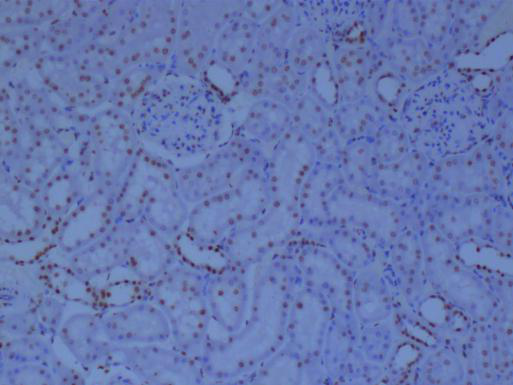

二、免疫組化:細(xì)胞與組織中的分子指紋

免疫組化技術(shù),則更多地被用于組織和切片水平的分析。通過特異性抗體與抗原的結(jié)合,結(jié)合顯色系統(tǒng),可以在組織切片上呈現(xiàn)出目標(biāo)蛋白質(zhì)的表達(dá)情況,為疾病的診斷和病理學(xué)研究提供重要依據(jù)。

②組織定位:能夠在組織切片上呈現(xiàn)目標(biāo)蛋白質(zhì)的分布和表達(dá)情況,對(duì)于疾病的定位診斷具有重要意義。